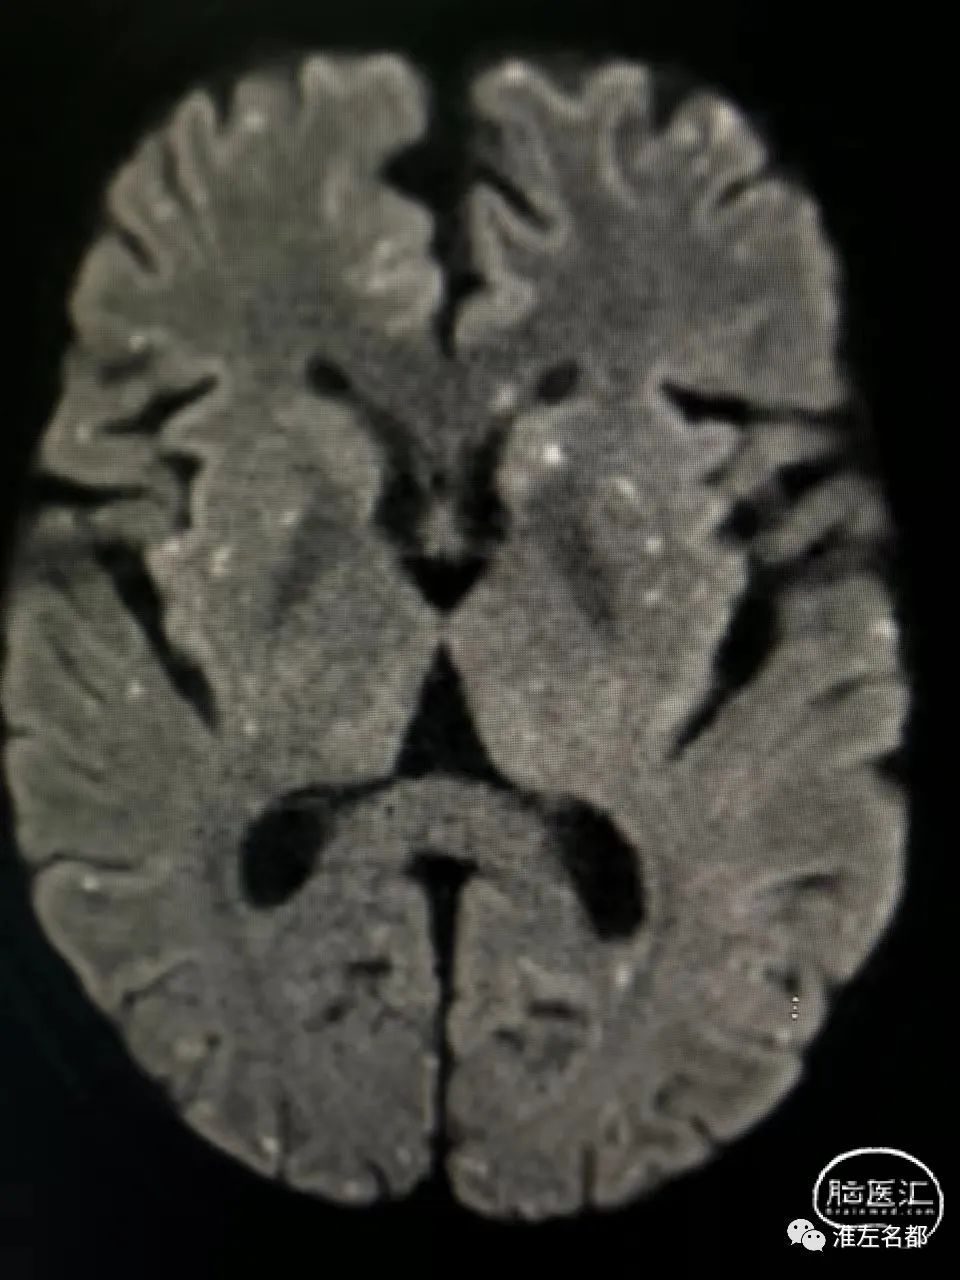

脑DWI:双侧半球皮质和皮质下弥漫分布的点状急性微小梗死灶。

第一,心源性栓塞梗死:患者心电图、心脏超声和心梗组合均提示心肌梗死,而心肌梗死是重要的心源性脑栓塞原因;该患者急性梗死病灶累及双侧半球多个脑动脉供血区,这个特征也是支持心源性栓塞的。

第二,还有一种可能的机制是,与肝癌栓塞治疗相关的反常栓塞:肝癌的肿瘤组织内是可能存在异常动-静脉瘘的,此时微小的球状介入栓塞材料就能通过这种瘘,经肝静脉进入下腔静脉和右心房,如果同时合并卵圆孔未闭,栓塞微球可经未闭的卵圆孔进入体循环,进而栓塞全身各个器官,包括脑和心脏。上述机制的支持点包括:患者53岁中年男性,而很大比率中-青年人群会合并卵圆孔未闭;患者术前无心脏疾病和心血管危险因素,术后即胸闷气促,这可能与介入用微球栓塞心肺的供血血管有关;由于微球直径很小,只会导致脑动脉远端的微小血管闭塞,所以脑梗死的范围很小,且弥漫分布。